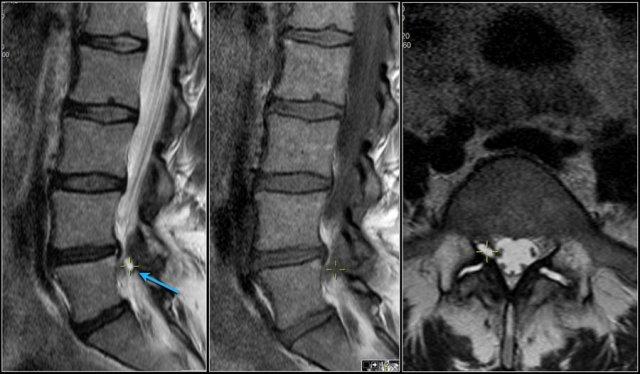

Sử dụng điểm đánh dấu

Khi phát hiện một bất thường, việc sử dụng điểm đánh dấu tương ứng với cùng một vị trí trên các chuỗi xung khác có thể rất hữu ích.

Nếu phóng to hình ảnh, bạn sẽ thấy dấu thập màu vàng nhỏ, cho biết bạn đang quan sát đúng vị trí đó trên chuỗi xung khác.

Trong trường hợp này, rễ thần kinh L5 bên phải bị chèn ép bởi một nang hoạt dịch (synovial cyst), là hệ quả của thoái hóa khớp mỏm khớp kèm tràn dịch trong các khớp gian đốt sống.